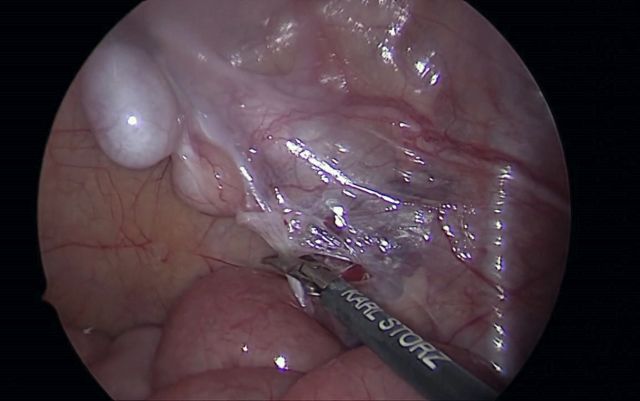

Shehata-Technik als vielversprechende Alternative beim intraabdominalen Hoden